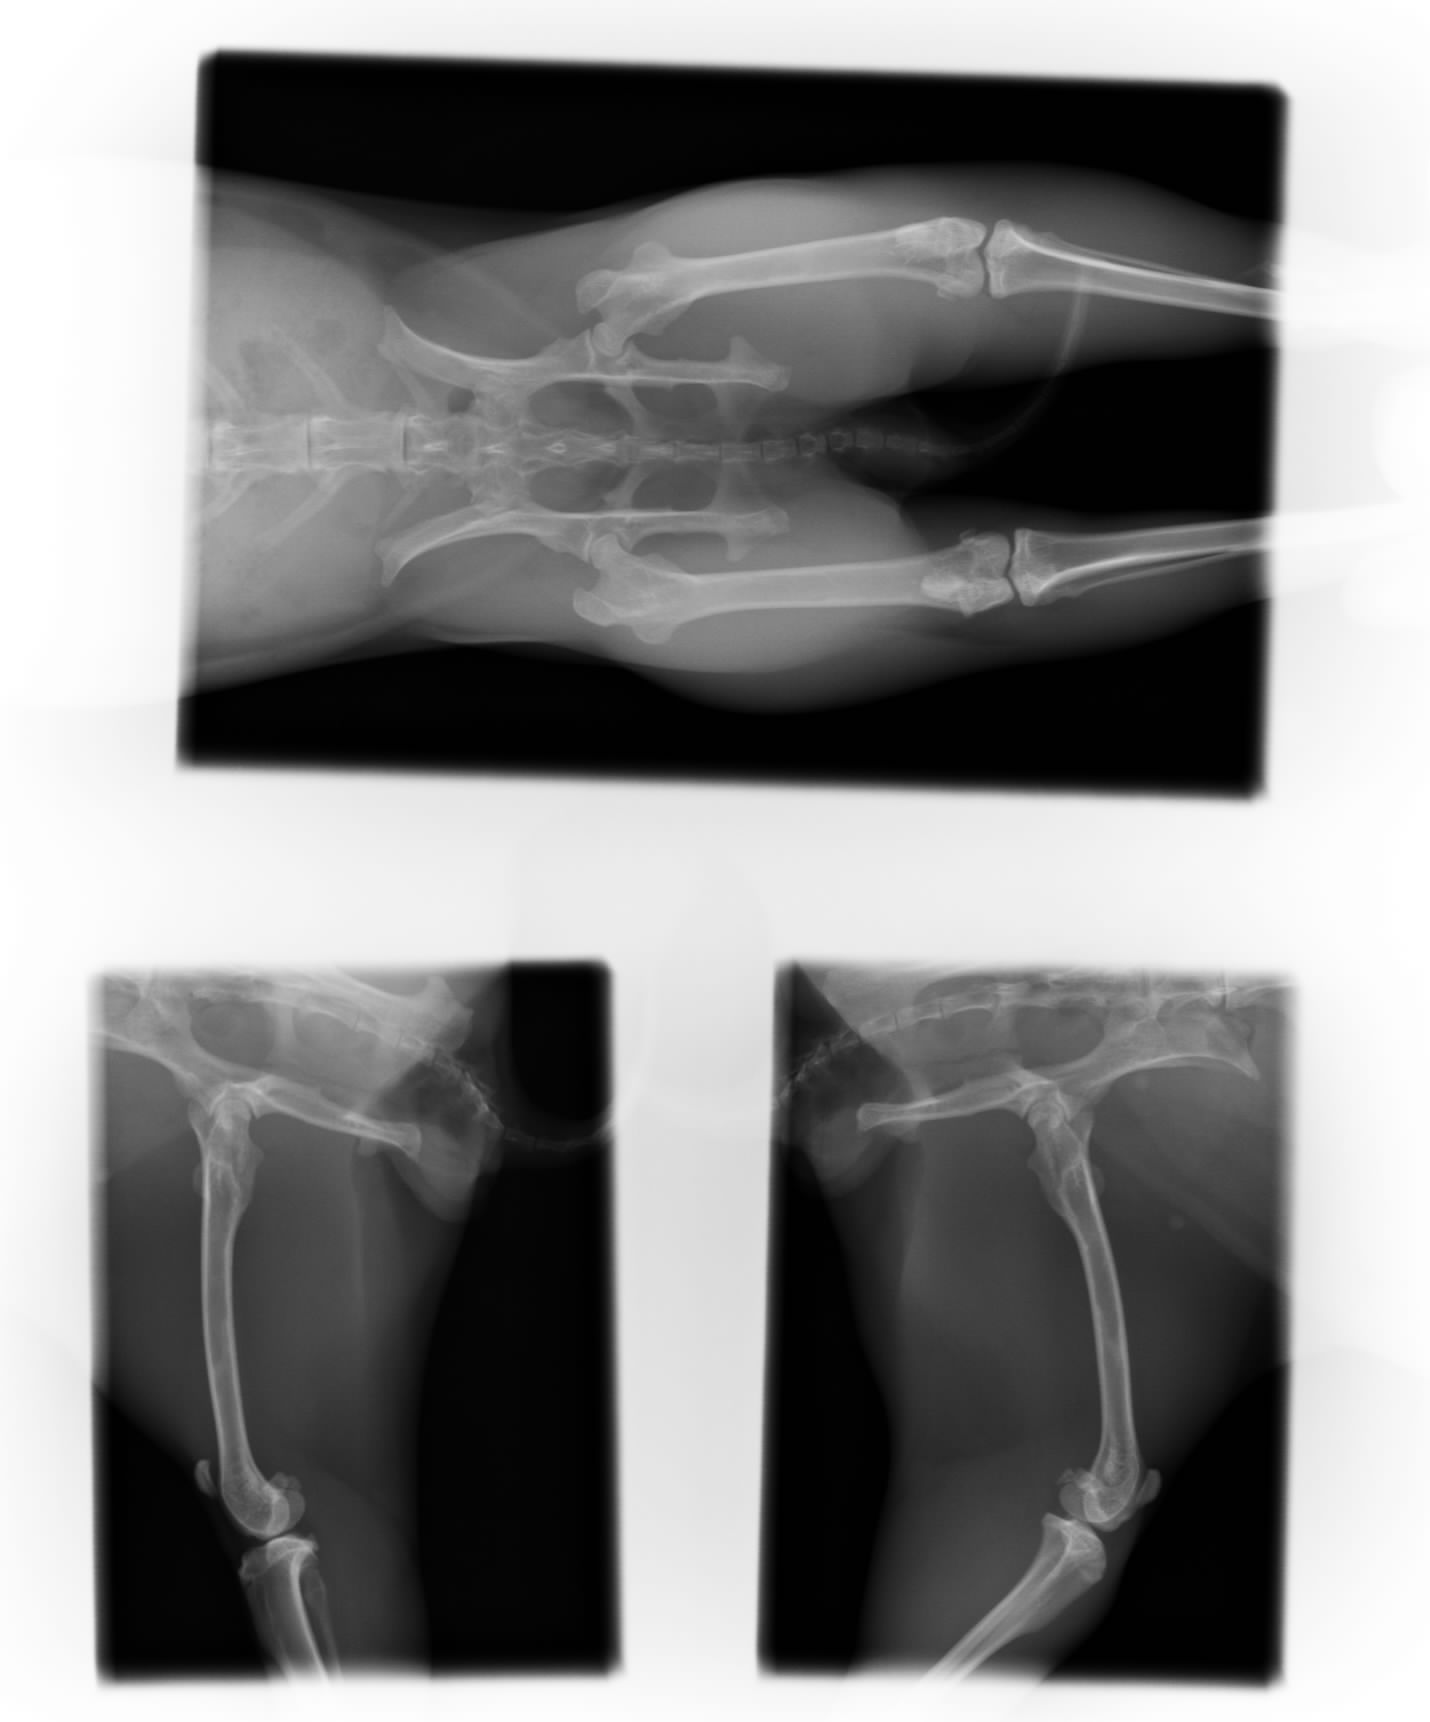

どこの骨が骨折かな?

骨盤や大腿骨は正常

ここの骨かっ

脛骨と腓骨の骨折

レントゲン検査では良さげな写真